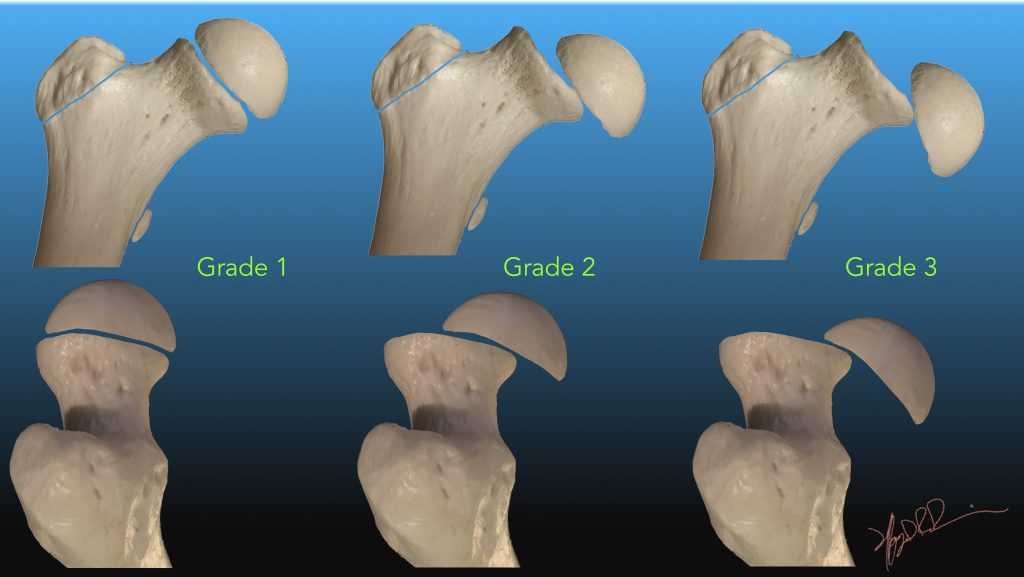

Femoroacetabular Impingement After Slipped Upper Femoral Epiphysis

boneandjoint.org.uk

boneandjoint.org.uk